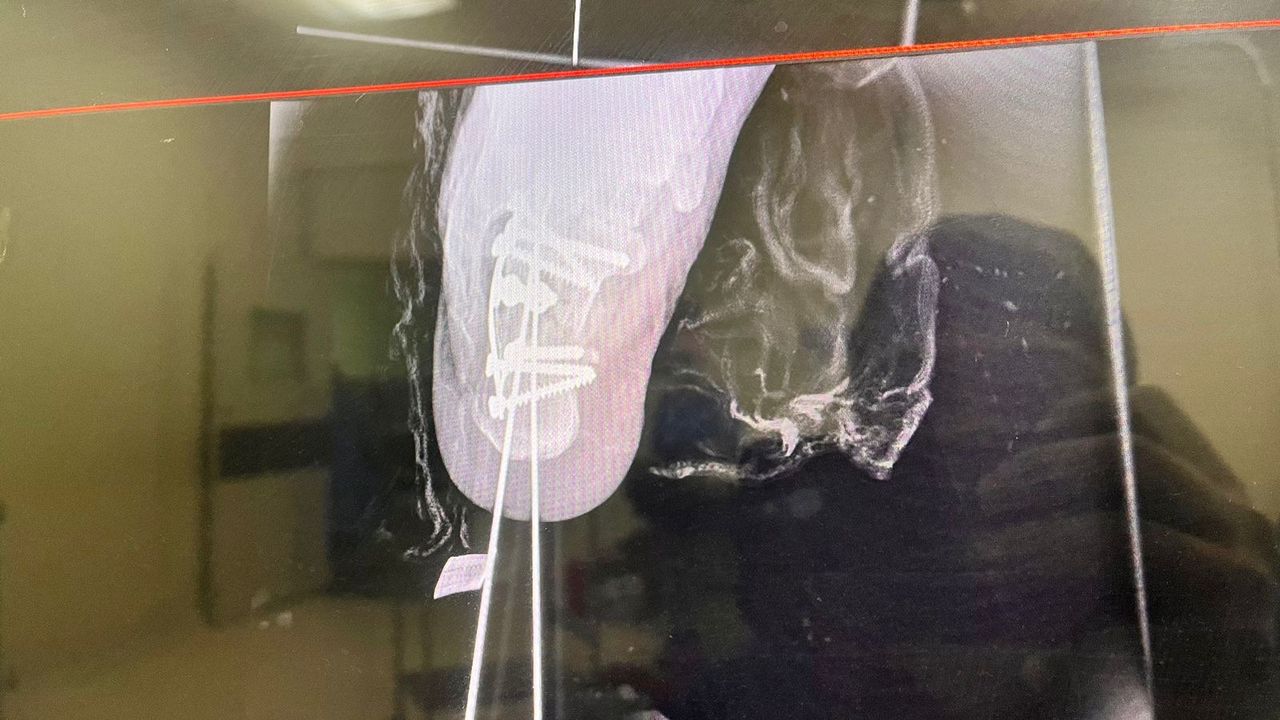

• Cirugía de pie y tobillo

Su forma de explicar es muy detallada y también su tiempo para analizar tu historial clínico. Me explicó muy bien los pasos a seguir en mi recuperación por fractura y debilidad en el tobillo.

• Clínica CEMIM | Especialistas Médicos Primera visita Ortopedia  •